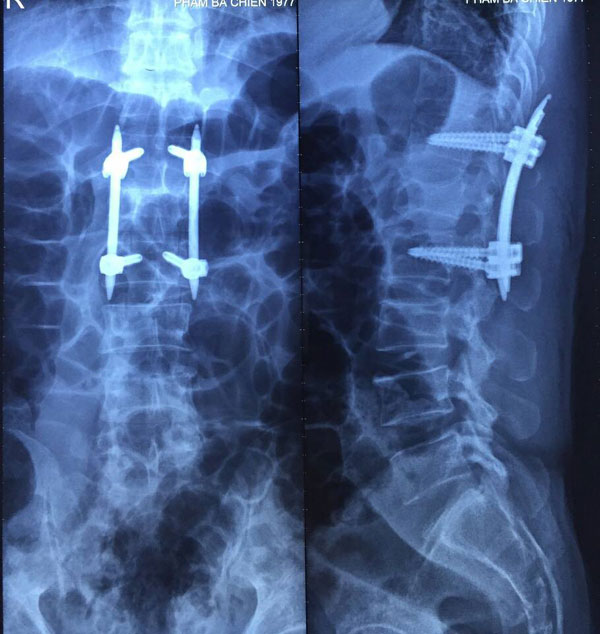

| Phim chụp cột sống bệnh nhân bị tai nạn lao động. Ảnh: Hiền Minh |

Gần đây nhất, là trường hợp bệnh nhân P.B.C, 40 tuổi, nhập viện cấp cứu ngày 20/11do tai nạn lao động, ngã thang từ độ cao 4m. Qua thăm khám lâm sàng kết hợp với các phương pháp chẩn đoán hình ảnh hiện đại, các bác sỹ chẩn đoán anh C bị chấn thương cột sống-vỡ đốt sống L1 mất vững.

Tuy nhiên, với phương pháp phẫu thuật cố định cột sống bằng vít qua da bằng hệ thống Sextant, sẽ rút ngắn thời gian phẫu thuật cho bệnh nhân, chỉ còn 1,5h, bệnh nhân phục hồi nhanh.

Với ca phẫu thuật của a C, chỉ sau chưa đầy 48 tiếng, bệnh nhân đã có thể đi lại bình thường. Sau 3 ngày phẫu thuật, anh C được ra viện.